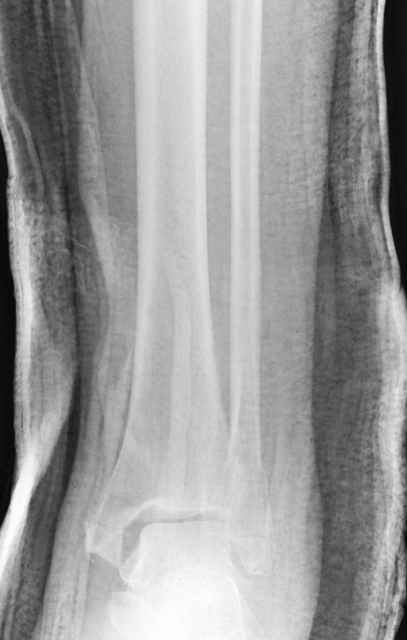

Dear all,40 y.o. man had sustained this terrible fracture falling from a motorbike.

Closed fracture.

This is really Pilon Fx (C3.3; the high energy and the extent of distal tibia comminution are defining it).

We have put his limb in traction.

After some days of traction I would like to insert an external fixator (I think a circular one instead of a monoaxial one, because of the multiplanar situation of the fracture).